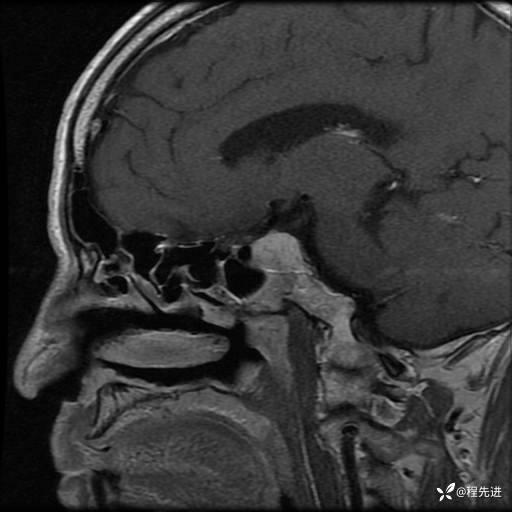

MRI平扫+增强:

T1增强: